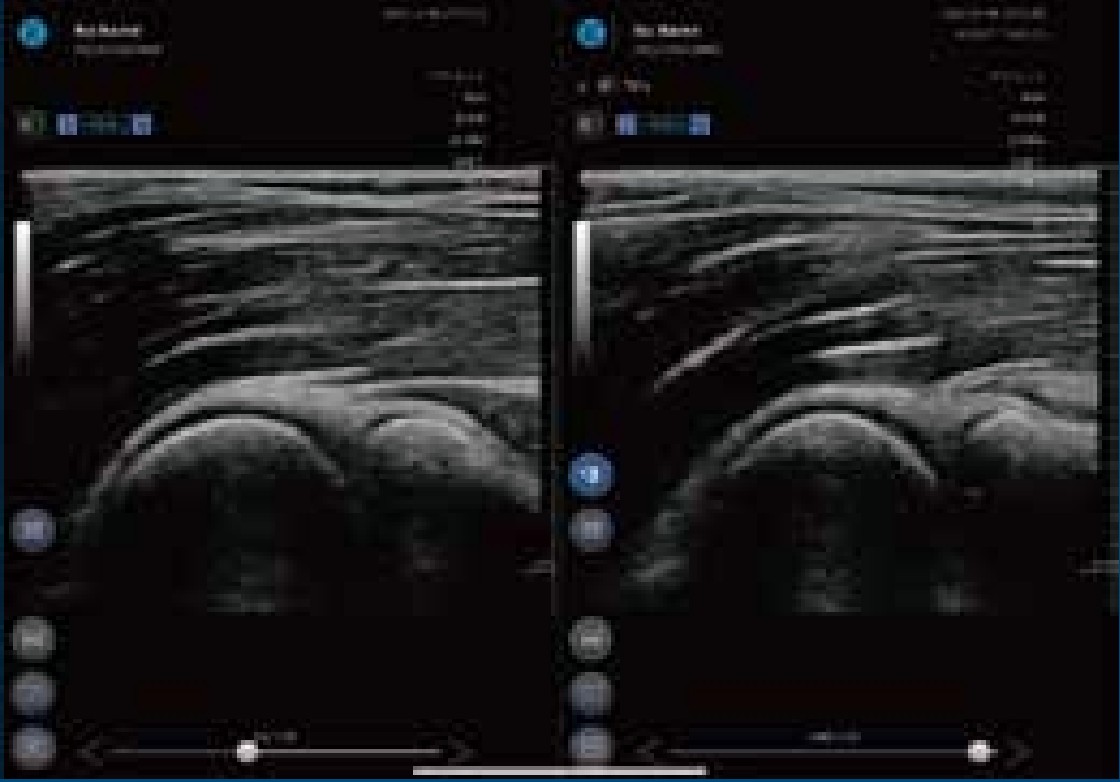

超音波画像診断装置

SONON身体の中をリアルタイムで“見て確認”

外傷や痛みのある部位、気になる部分の状態を確認できます。筋肉・腱・靭帯・関節など幅広く把握でき、より正確な評価と施術につながります。

- 放射線は一切使用しないので安心

- 数分で検査可能、小さなお子様にも安全

- 動かしながら確認でき、“使って痛い”原因を特定

- 成長期のお子様の身長の伸びしろ測定も可能

状態に応じて当院の判断で使用しますが、ご希望の方はお気軽にお申し付けください。